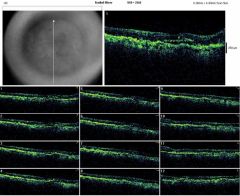

![]() OCTOD1 |

![]() OCTOD2 |